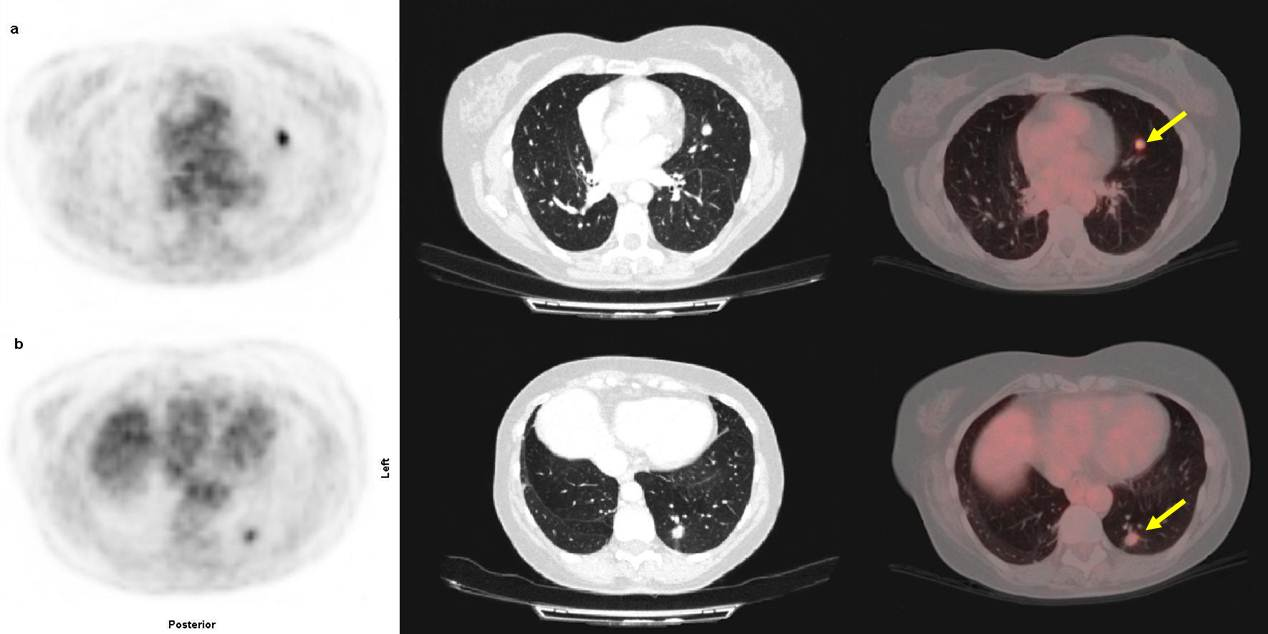

En este momento, a pesar de niveles normales de antígeno carcinoembrionario (CEA), se decide la realización de una tomografía por emisión de positrones (PET/CT) con 18-fluoro-2-deoxyglucosa (18F-FDG) para evaluar posible presencia de enfermedad en otras localizaciones. Se practicó un estudio de cuerpo entero en un equipo híbrido PET/CT (Siemens Biograph) una hora después de la administración intravenosa de 444 MBq de 18F-FDG. El estudio demostró dos nódulos hipermetabólicos en el pulmón izquierdo, el primero localizado en la língula de 1 cm de diámetro y con un “maximum stardardized uptake value” (SUVmax) de 7,6 (fig. 1a). El segundo nódulo se localizaba en el segmento posterobasal, con un diámetro de 1,3 cm y SUVmax de 2,8 (fig. 1b). El SUV del parénquima pulmonar era de 0,4.